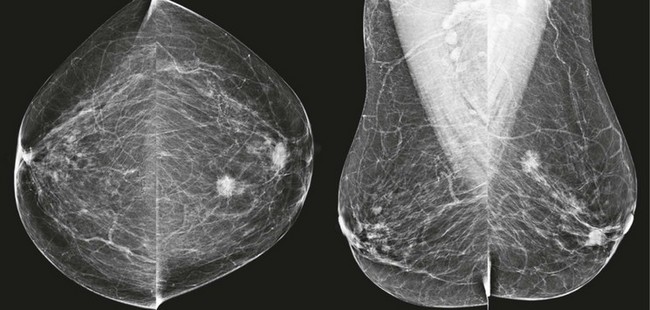

FIGURE 8-9 Waxing and Waning Cysts.

Some masses have enlarged while some have decreased in size. As long as the masses all have benign features and none are dramatically larger, recall is not necessary. This is BI-RADS 2.